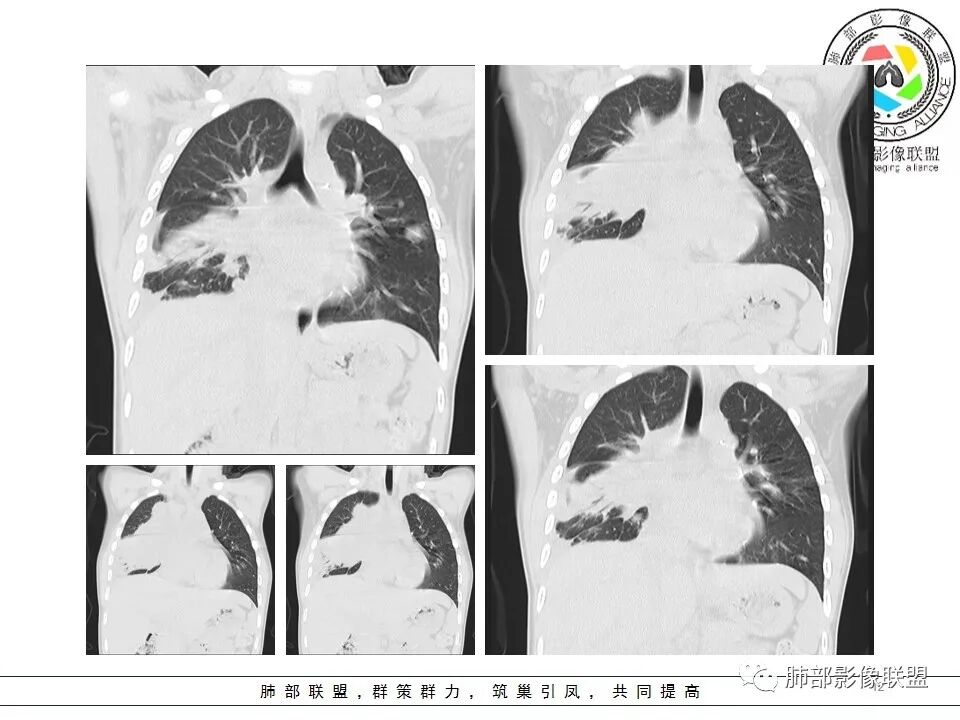

右前纵隔巨大软组织肿块,主要偏向右侧生长,边界不清,密度不均匀,内见大片状低密度坏死区及散在钙化灶,未见骨骼影及脂肪密度影。、双肺随机分布的转移瘤结节,右肺肺不张及右侧胸腔积液,提示恶性肿瘤病变伴双肺及胸膜转移。

前纵隔肿块常见的良性病变为畸胎瘤,恶性肿瘤有侵袭性胸腺瘤或胸腺癌、淋巴瘤、恶性生殖源性肿瘤、Askin(Pnet)瘤等。患儿9岁,30岁以下的胸腺肿瘤非常罕见。而且从病变密度不均,缺乏多结节堆积感,可见钙化等淋巴瘤的可能性不大。虽然这个病例缺乏增强及相关实验室检查,小儿前纵隔恶性肿瘤中恶性生殖细胞肿瘤相对常见,须鉴别的是Askin(Pnet)瘤,可结合有关HCG,AFP和LDH实验室检查帮助甄别。

四.纵隔生殖细胞肿瘤拓展

生殖细胞肿瘤多起源于多能性原始生殖细胞,纵隔生殖细胞肿瘤是性腺外生殖细胞肿瘤最常见的部位,好发于青年男性。生殖细胞肿瘤有精原细胞瘤、畸胎瘤、内胚窦瘤(卵黄囊瘤)绒毛膜癌、胚胎癌、及混合生殖细胞肿瘤,其中除成熟的畸胎瘤为良性,余生殖细胞肿瘤均为恶性肿瘤。

内胚窦瘤(卵黄囊瘤)

是高度恶性生殖细胞肿瘤,卵黄囊细胞是唯一产生AFP的细胞,所以AFP升高是卵黄囊瘤或含有卵黄囊成份的生殖细胞肿瘤最重要的特征,其中卵黄囊瘤一般大于1000ug/L;影像表现肿块体积往往较大,易坏死囊变,易侵犯周围结构及转移。

男性,12岁,绒癌伴双肺转移